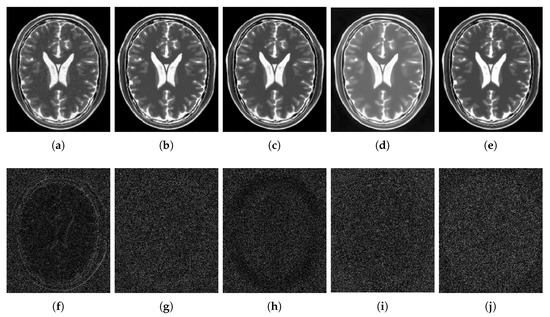

4.2.1. Synthetic Data

4.2.2. Real Data